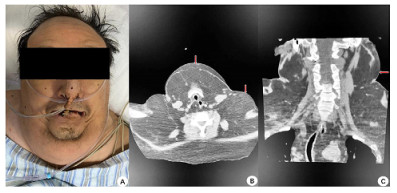

入院查体:患者呈昏迷状,双侧瞳孔等大等圆,直径3 mm,对光反射迟钝,颈部(图 1)和肩部(图 2)分别可见7 cm×4 cm及5 cm×6 cm大小软组织肿胀,质软,腹部及双侧大腿内侧(图 3)可见5 cm×6 cm软组织肿胀,质软,双肺呼吸音粗,双肺可闻及少许湿啰音,心律齐,各瓣膜听诊区未闻及病理性杂音,腹部膨隆,腹部查体不配合。入院后相关检查见表 1,腹部超声提示脂肪肝,心脏超声示左室壁运动弥漫性减低、左室壁肥厚,左室射血分数47%。

| A:患者下颌及颈部脂肪隆起;B:颈部CT平扫(轴位-下颌及颈部皮下脂肪影增多);C:颈部CT平扫(冠状位-颈部皮下脂肪影增多) 图 1 患者下颌及颈部病变(红色箭头所示) |

入院后给予呼吸机辅助通气,美罗培南抗感染、维生素B1肌注、营养支持等治疗,患者神志逐渐恢复,可自主睁眼,但不能按指令动作,呼吸机条件逐渐下调,并于2月4日成功脱机拔管。复查相关实验室检查见表 2,行头颅CT示脑室系统扩大,脑沟、脑裂稍宽,脱髓鞘改变;颈部CT示颈部大量脂肪沉积(图 1、图 2);胸部CT示双肺散在斑片影,考虑感染;腹部CT示腹腔及皮下脂肪影增多(图 3)。结合患者既往长期大量饮酒史、查体及影像学表现,考虑诊断:马德龙病、Wernicke脑病。患者不能配合指令动作,未行头颅磁共振检查。